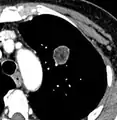

Thin slice and maximal intensity projection of a lung nodule, the latter better visualizing vascular convergence.[9]

• Vascular convergence is where vessels converge to a nodule without adjoining or contacting the edge of the nodule, and is mainly seen in peripheral subsolid lung cancers.[9] It reflects angiogenesis.[9]